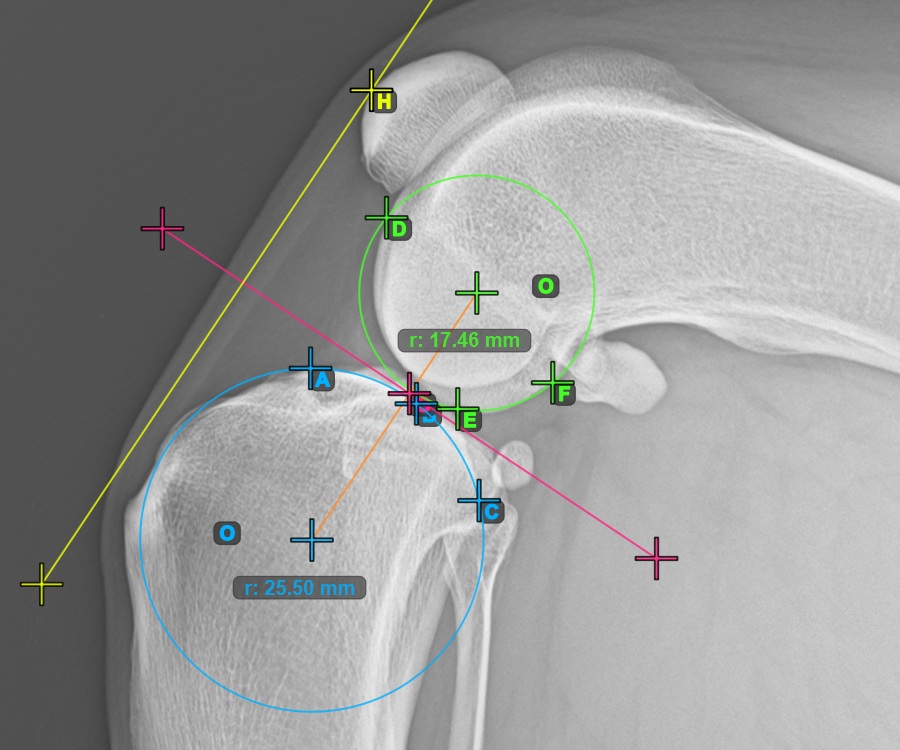

Continue by marking the three points on the articular surface of the Condylus Femoris.

Mark the three points on the main condylus of the femoral bone (Condylus Femoris). Regardless of the order, make sure to mark the most cranial point, the most caudal point and the midpoint of the Condylus Femoris. A circle will be automatically constructed based on the three placed points.

The image below represents a typical placement of the three points on the Condylus Femoris.

Mark one point in front of the joint on the common tangent between the two circles. A line will be drawn automatically through the marked point.

The image below represents a typical placement of the point on the common tangent between the two circles.